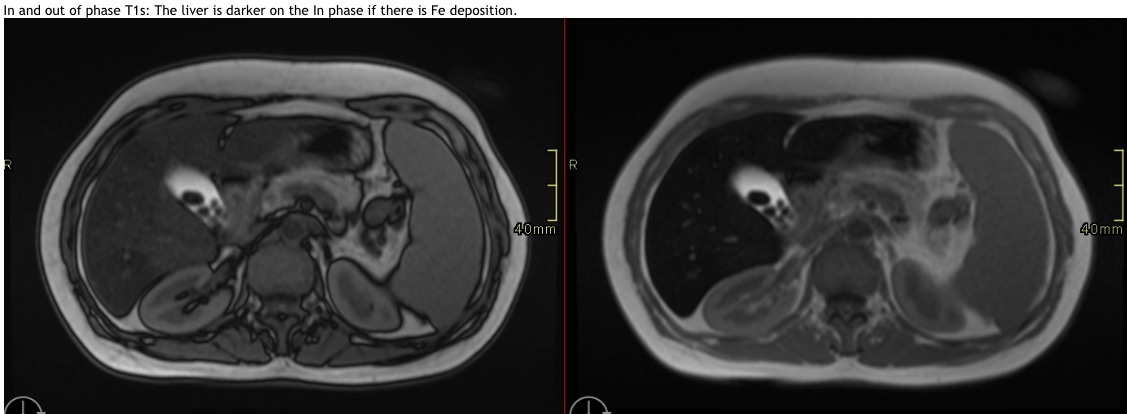

In and out of phase T1s: The liver is darker on the In phase if there is Fe deposition.